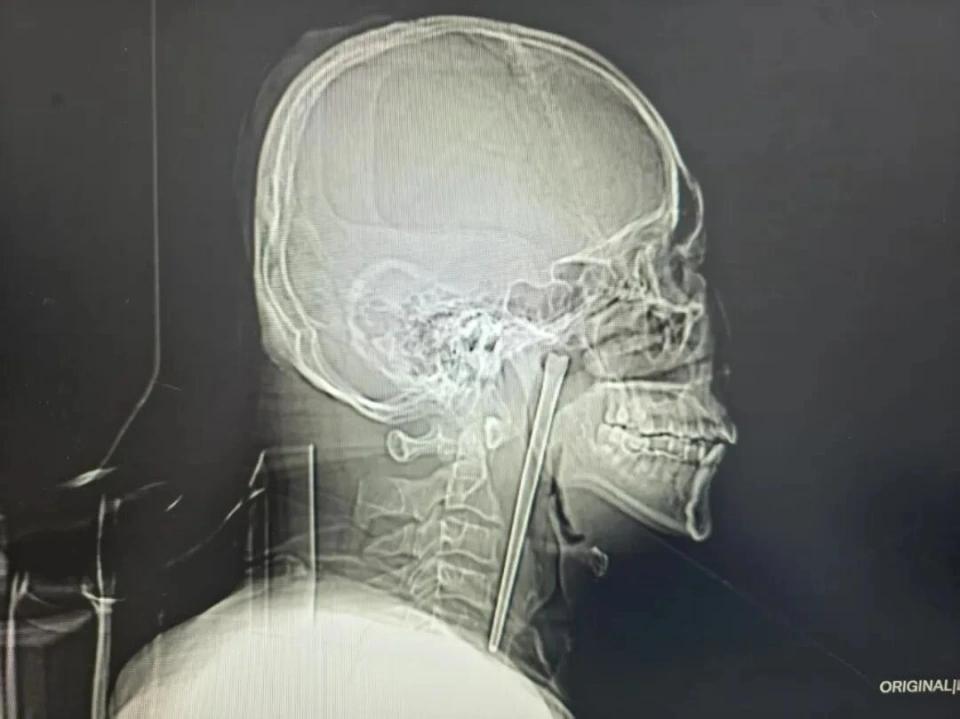

大连一男子8年前误食一根筷子在嗓子眼,男子一直忍忍忍,最后实在疼得受不了去医院后,医生惊呆了,我也看呆了! 这是一个用"忍"字撑起来的故事。八年,2920天,一根12厘米长的金属筷子,一直竖在王先生的喉咙里。 你没看错,是一整根筷子,不是骨头,不是鱼刺,是咱们平时吃面条用的那种不锈钢筷子。 八年了,王先生一直觉得喉咙里"有点东西"。 这东西什么时候来的,他自己最清楚。八年前那次吃饭,他一不留神,把整根金属筷子咽了下去。 当时就噎得就够呛,喉咙疼,去医院一看,医生说筷子在里头,想取出来得切开脖子做手术。 王先生摸了摸脖子,想了想有点怕,还是算了吧。 这一算,就是八年。 这八年里,他养成了个习惯——把喉咙里偶尔的异物感、隐隐的疼痛,都算在喝酒的账上。喝多了嘛,喉咙不舒服正常。他就这么自我说服着,一天天过去了。 直到前几天早上,那种疼变了。 不是"喝了酒第二天的那种疼",是吞咽的时候像刀刮,不吞咽的时候也有个东西在那梗着,歇多久都下不去。 他这才慌了神,跑到了大连理工大学附属中心医院。 医生拿喉镜一照,也惊呆了——王先生右侧咽后壁上方,软腭后头,一根金属筷子嵌在那儿,露出来大概3厘米。整个筷子量出来,12厘米。 也就是说,这八年,这根筷子一直斜插在他的咽部,一头扎进组织里,一头悬在那儿,哪儿也去不了,就这么待着。 王先生这些年咽下去的每一口饭、每一杯酒,都从它旁边经过。 医生分析,这次之所以突然疼得厉害,可能是时间太久,异物开始刺激周围组织,再拖下去,旁边就是血管和重要结构,一旦感染或者出血,麻烦就大了。 但这次王先生运气不错。医生考虑到他八年前就是因为怕开刀才放弃的,专门给他设计了个经口腔取的微创方案,不用切脖子做手术。 手术台上,医生小心翼翼地剥离、牵拉,最后把那根12厘米的筷子完整取了出来。 整个过程出血极少,王先生醒来后,喉咙里那种"有东西"的感觉,第一次消失了。 其实这事说起来,最让人唏嘘的不是那根筷子,而是王先生这八年是怎么"忍"过来的。 咽部异物感、偶尔的隐痛——这些信号他全收到了,但他给这些信号找了个最省事的解释:喝酒喝的。毕竟他有长期饮酒的习惯,喉咙不舒服,太正常了,正常到他懒得去分辨这到底是酒的问题,还是那根没取出来的筷子的问题。 医学上有个词叫"咽异感症",说的就是喉咙里总觉得有东西,咽不下去吐不出来,很多人最后都归因于慢性咽炎或者心理作用。但医生反复提醒过,这种诊断必须建立在排除器质性病变的基础上——也就是说,你得先确定里头没长东西、没卡东西,才能说这是"感觉"。 王先生的情况恰好反过来。他明明知道里头有东西,却硬是说服自己那只是"感觉"。 而这让我想起另一个病例,有个人异物在喉咙里藏了17年,也是各种不舒服,也是到处看,也是没查出来,最后因为别的毛病才被发现。 那17年里,他因为反复的不适和查不出原因,生活过得一塌糊涂,婚姻都出了问题。 比起他来,王先生算是幸运的——至少他知道那根筷子在哪,只是选择不去管它。 不过话说回来,有多少人正在把自己身体发出的信号,归类于"最近太累了""老毛病了""喝点酒就这样"? 还有个细节也很有意思。王先生这次去医院,不是因为八年的"习惯性不适",而是因为那种不适变了——变得更疼,更持续,休息也缓解不了。是这种"不一样"把他推到了医院。 对于此事,你们怎么看?